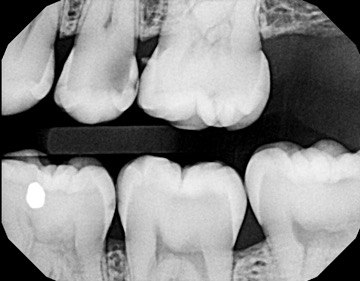

1. Which surfaces shows dental caries?